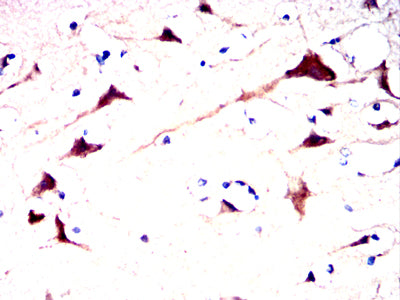

- Immunohistochemical analysis of paraffin-embedded human brain tissues using AFP mouse mAb with DAB staining.